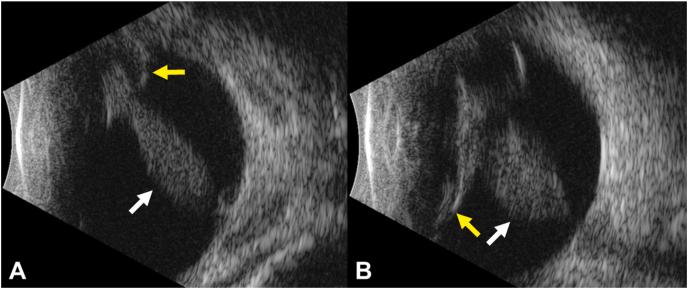

A 3-day-old boy born at full term had bilateral retrolental fibrovascular plaques. Surgery with lensectomy and vitrectomy revealed bilateral, closed funnel retinal detachments consistent with a clinical diagnosis of Norrie disease. In addition, the baby had congenital heart defects, hearing loss, and dysmorphic facies. His mother carried a clinical diagnosis of Kabuki syndrome. Genetic testing of the baby revealed an Xp11.3 microdeletion that included the and genes, confirming the baby had both Norrie disease and X-linked Kabuki syndrome. The mother was found via ultrawide-field fluorescein angiography to have asymptomatic peripheral retinal vascular anomalies, consistent with -associated familial exudative vitreoretinopathy (FEVR).